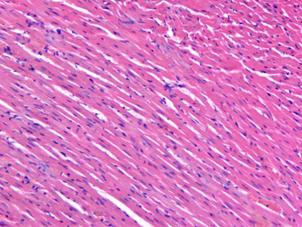

樣本:大鼠心肌

圖1 HE染色圖 100X

樣本中細胞核被蘇木精染成鮮明的藍色。細胞質被伊紅染成深淺不同的粉紅色至深紅色。對比鮮明??梢郧逦^察到組織形態,符合HE染色結果的要求。